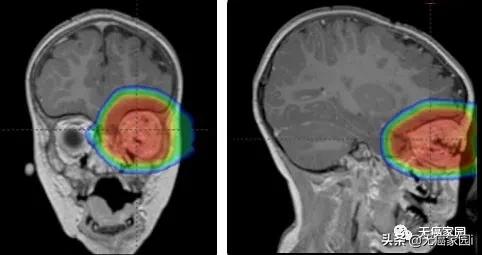

通常建议对脑肿瘤进行质子治疗,因为脑肿瘤靠近脆弱且至关重要的正常组织和结构。更重要的是,原发性脑肿瘤通常会在大脑中开始并持续存在,从而使他们更适合接受质子治疗。